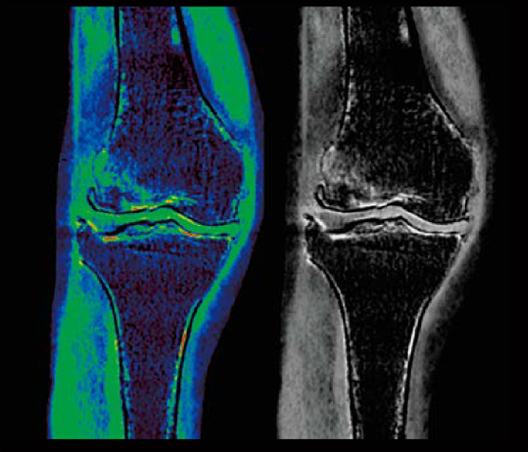

Humeral greater tuberosity fracture

Tibial plateau fracture

Femur fracture (Dual-Energy)